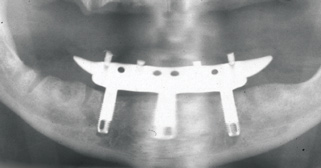

Fig 2. Four vertical machined-surface osseointegrated implants placed in 1983 penetrated the inferior cortex up to 3 mm to 4 mm in depth, immediate postoperative.

Figure 2

The Toronto Conference in 1982, chaired by Professor George Zarb and presented by Professor Per-Ingvar Brånemark, was a seminal event that changed edentulous treatment planning concepts irrevocably. No longer was it necessary to rebuild lost bone through grafting alone in either arch. The severely atrophic mandible, for example, could be treated with as few as four implants used to support a bone-sparing prosthesis through integrated tooth analogs, as demonstrated in Figure 1 through Figure 3. Here, an 81-year-old patient presented with severe mandibular atrophy (Figure 1) from denture wear since a very young age and had a history of being unable to manage a mandibular prosthesis despite numerous attempts at new denture construction. Four vertical machined-surface osseointegrated implants were placed in 1983 by Professor Brånemark, and all four penetrated the inferior cortex up to 3 mm to 4 mm in depth, as shown on the immediate postoperative panoramic film (Figure 2). At 4 years and 5 months, reparative bone had formed to the apices of all implants (Figure 3), and all of them remained in uncompromised function until the patient passed away at age 90.